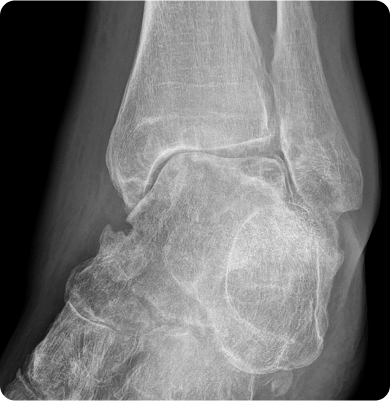

발목관절염

발목을 구성하는 뼈와 뼈 사이의 연골이 손상되어 염증이 생기고 시간이 지나면서 점차적으로 발목 관절의 기능이 떨어지는 질환

주요원인

발목에 반복적인 부하가 가해지거나 이전에 발생한 발목 부상, 특히 골절이나 염좌로 인해 관절의 구조가 변형될 때 발생합니다.

주요증상

• 장시간 서 있거나 걷는 것이 어려워지고, 일상 생활에 지장이 생길 수 있습니다.

• 발목에 소리나 불편함이 생기고 걷거나 운동할 때 불편함을 느낍니다.

• 발목이 붓거나 열감이 느껴질 수 있습니다.